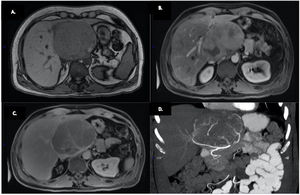

A) Imagen de resonancia magnética contrastada con gadolinio, donde se observa una masa hepática de 10 × 9 × 10 cm, localizada en el lóbulo caudado, fuera de fase, hipointensa en secuencia en T1 e isointensa en secuencia en T2. B) realce en la fase arterial. C) Lavado en fase venosa portal tardía. D) Vista coronal de la imagen por TC. Se visualizó un tumor de 10 cm en el lóbulo caudado, en íntima relación con las arterias gástricas derecha e izquierda.

Un varón de 49 años con dolor abdominal en el cuadrante superior derecho fue atendido en el departamento de urgencias. El paciente tenía historia de epilepsia tratada por 20 años con 300mg/día de fenitoína. Un ultrasonido (US) abdominal mostró una masa isoecoica de 6×5×5cm en el lóbulo hepático izquierdo, y una tomografía computarizada (TC) reveló un hemangioma hepático. Dos años después, el paciente reportó dolor epigástrico posprandial. Un nuevo US identificó un incremento de 5cm en la lesión hepática. Una resonancia magnética contrastada con gadolinio mostró una masa hepática heterogénea de 10×9×10cm en el lóbulo caudado, hipointensa en secuencia en T1 e isointensa en secuencia en T2, con realce en la fase arterial y lavado en la fase venosa portal tardía (fig. 1). Una TC con contraste intravenoso mostró el tumor hepático íntimamente relacionado con las arterias gástricas izquierda y derecha. La vena porta y los vasos esplénicos no estaban comprometidos (fig. 1). Los estudios de laboratorio fueron normales, excepto por una hipertransaminasemia leve (ALT: 98U/l, AST 174U/l). Las pruebas para virus de hepatitis B y virus de hepatitis C fueron negativas y los valores de alfafetoproteína fueron normales.